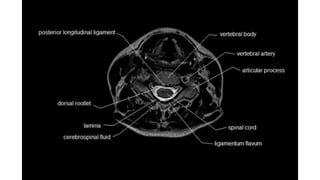

MRI spine and sequences

Spine sequences

• T1

• T2

• STIR

• T1C

• DIXON

• DWI

• SWI

59